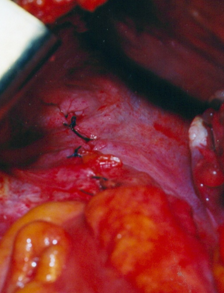

Η στένωση του τερματικού ειλεού διακρίνεται ανάμεσα στα δάκτυλα του χειρουργού (Ευγενική παραχώρηση Dr. V. Penopoulos)